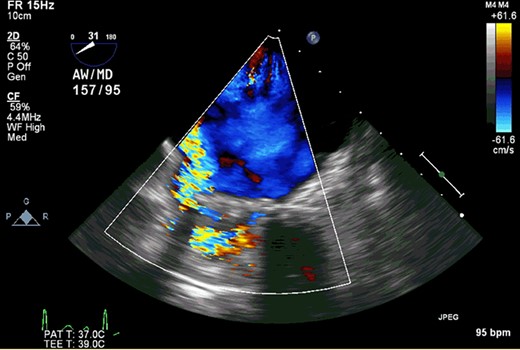

The patient was a 56-year-old male with a history of infectious endocarditis of aortic and mitral valves complicated with aortic root abscess. He underwent aortic root replacement with an aortic homograft and MVR with a 27-mm St. Jude mechanical valve. At 7 years after the surgery, he presented to the hospital due to worsening shortness of breath, dark urine and swollen legs. He had hemolysis with lactate dehydrogenase of >1000 U/L. Transesophageal echocardiography demonstrated that the mechanical prosthesis had focal dehiscence at the inferior and inferoseptal margins with severe perivalvular leakage (Fig. 1). The aortic homograft function was well preserved without aortic insufficiency. Right heart catheterization also revealed elevated pulmonary artery and filling pressures (right atrial pressure, 15 mmHg; right ventricular pressure, 88/15 mmHg; pulmonary artery pressure 88/33 (52) mmHg and pulmonary capillary wedge pressure, 33 mmHg). Based on these symptoms and findings, we decided to perform reoperative MVR.

Transesophageal echocardiography demonstrated that the mechanical prosthesis had focal dehiscence with severe perivalvular leakage.